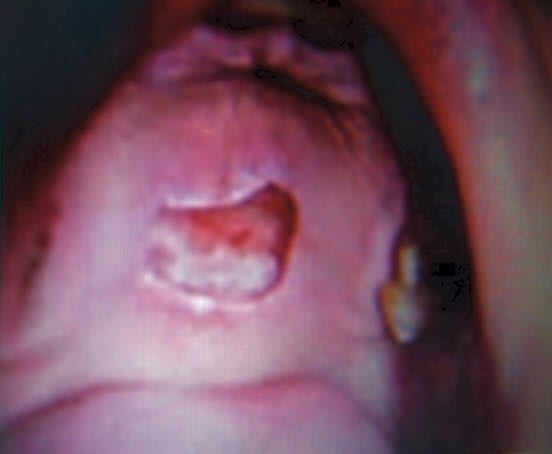

Oups erreur (qu'est-ce qu'elle fout dans mes fichiers???), non après cela c'est nécrosé et creusé sur toute la surface de la lésion.

Joint une photo pourave (photo d'écran je n'arrive pas à sortir l'image correspondante) mais c'est cela, nécrosé et creux,indolore.

Une sérologie fut demandée.

Puis lésion (ulcération) torpide une quinzaine de jours.

Ensuite en 3 à 4 semaines nous avons eu une cicatrisation, je dois avouer que nous avons bien flippé vu l'aspect du truc.

Tu as raison, la première c'est ma patiente.

La seconde c'est une photo pour monter l'aspect de la lésion, mais ce n'est pas la même patiente. Ce qui doit être retenu pour la seconde photo c'est uniquement l'aspect de la lésion.

C'est une chose rare, et il faut penser patho.